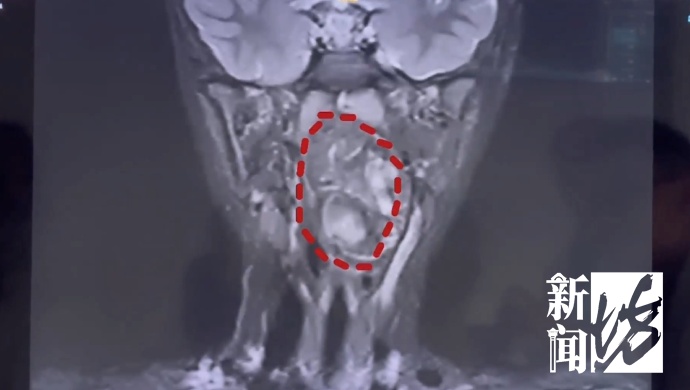

经诊断,这颗肿瘤有脂肪,有软骨,是一颗由生殖细胞长成的畸胎瘤。也就是说,小亮在妈妈肚子里时可能是一对双胞胎,一个发育成正常的人,另一个残留在咽部旁间隙里面,发育成了畸胎瘤。

医生说,虽然畸胎瘤绝大多数是良性,但多生于腹腔内。像这样长在儿童咽喉部,而且又这么大的,极其罕见。肿瘤还在长大,如不及时干预,孩子恐有生命危险。